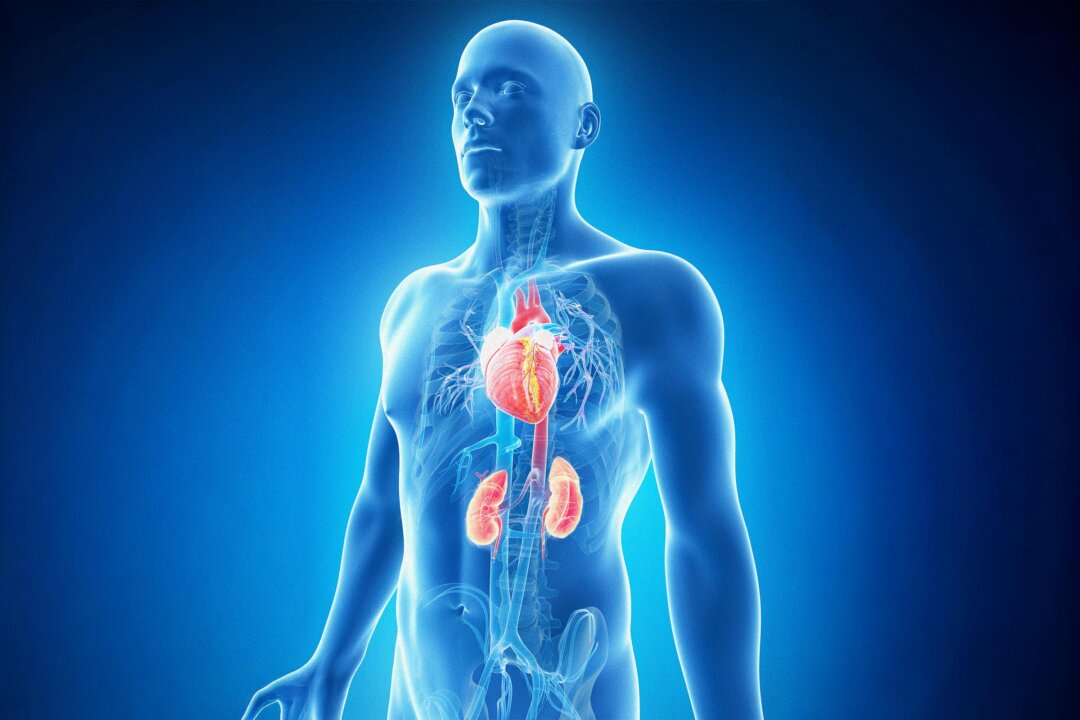

The American Heart Association (AHA) has issued a warning regarding a new health concern affecting nearly all American adults, yet remains largely unknown to the public. The condition, identified as cardiovascular-kidney-metabolic (CKM) syndrome, is a cluster of interconnected diseases that significantly increases the risk of serious health complications, including heart failure.

CKM syndrome encompasses several chronic conditions that often co-occur: heart disease, kidney disease, diabetes, and obesity. These illnesses are interrelated and can exacerbate one another, creating a cycle that increases the likelihood of severe cardiovascular events such as heart attacks and strokes. The AHA first defined CKM syndrome in a 2023 Presidential Advisory, aiming to raise awareness of this critical health issue.

The AHA’s findings reveal a concerning trend: while these diseases are often treated separately, their interconnected nature necessitates a more holistic approach to health care. The organization emphasizes the importance of recognizing CKM syndrome as a unified condition rather than a collection of individual diseases.

The implications of CKM syndrome are significant. Individuals suffering from one or more of the associated conditions face a heightened risk of heart failure, which can lead to serious health complications and increased mortality rates. The AHA’s survey underscores the importance of early detection and intervention, which could dramatically improve outcomes for millions of Americans.